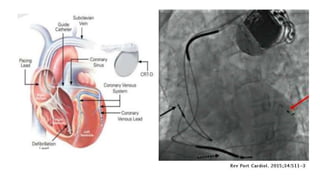

This document provides an overview of heart failure. It begins by outlining the objectives of understanding pathophysiology, classification, therapeutic targets, and initiating guideline directed medical therapy. It then discusses the anatomy, myocardial mechanics, effects on physiology, and introduction to heart failure. Classification systems such as ESC and AHA/ACC are presented. The document discusses heart failure in India, hospitalization risk, definition, and why ejection fraction is used for classification. It covers the pathophysiology, signs and symptoms, assessment, biomarkers, ECG, CXR findings, echocardiogram evaluation, treatment approaches for acute and chronic heart failure, guideline directed medical therapies including drugs, and SGLT2 inhibitors.